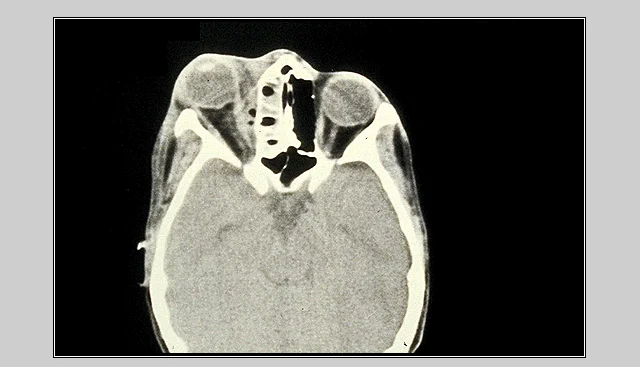

Management of Orbital Cellulitis

- CT Scan.